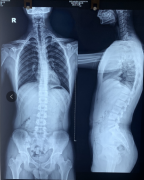

15岁少年军人梦差点被破灭,凶手竟然是它!

一向风度翩翩的安主任,刚才在门诊竟然生气了。这到底是怎么回事呢?赶紧跟我来看看吧! 原来他今天接诊了一位脊柱侧弯的患者飞飞,患者说自己从小喜欢看军旅题材的电视和电影,